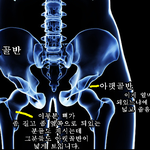

[댓글부탁]

골반

보고 고관절이라 헛소리하는 인간들 필독